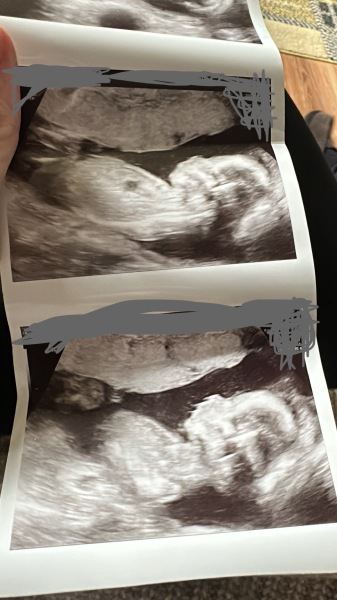

Boopbeep96 · 03/07/2025 23:11

Just another update, had an early assurance scan on Sunday at 8w2days and everything is perfect with baby. ❤️